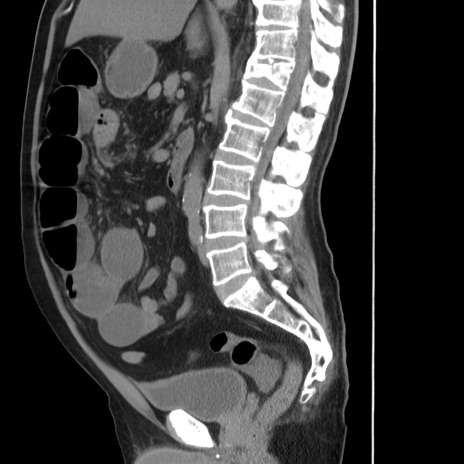

症例20(矢状断像)

【症例】 60歳代男性

【主訴】 腹部膨満、嘔吐

【現病歴】5日前頃より倦怠感を認め食事量減少し4日前の朝嘔吐、食事摂取困難となった。 3日前近医受診し点滴施行され整腸剤などを処方された。 当日他院を受診し、腹部膨満著明、炎症反応の上昇(CRP10.8、WBC11200)あり、紹介受診となる。

【既往歴】 躁うつ病(抗精神病薬多数内服あり)

【身体所見】 意識JCS1 受け答えがはっきりしないBP 111/57mHg、 P 67bpm、、BT35.2°C、SpO2 97%(RA)、 腹部:膨隆、打診で鼓音あり、全体的に圧痛有り、腸蠕動音(-)、反跳痛ははっきりせず。

【データ】WBC 11400、CRP 14.20